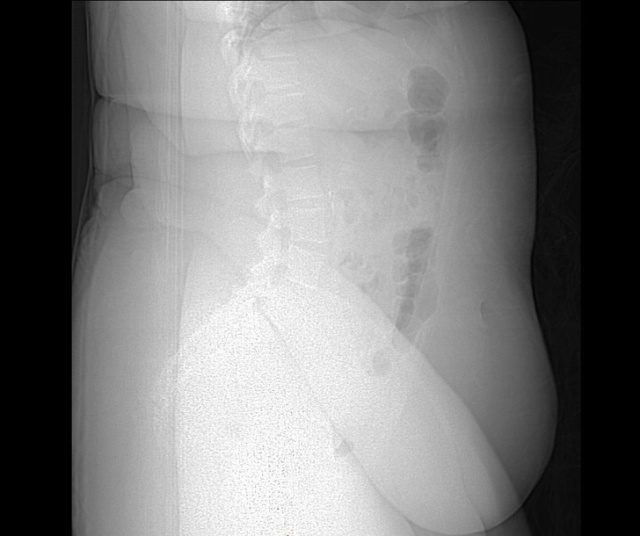

Рентгеновский снимок человека с ожирением. Обратите внимание, что кости плохо видны из-за избыточного количества жировой ткани